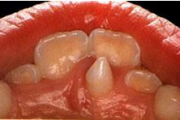

Vali sind huvitav pilt ja me näitame sellega seotud haigust ja sümptomeid